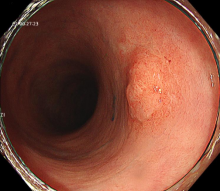

图示:放大胃镜下早期胃癌的微结构排列紊乱,微血管呈现扭曲、形态不规则。